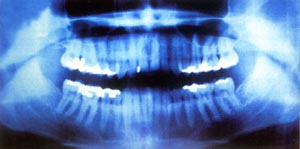

受这次偶然发现的激励,伦琴放下其他研究项目,集中精力调查X射线的特性。经研究他发现:X射线能使许多物质发光;X射线可以穿透不透光物质,他特别注意到,X射线能够透过他的肉体,只是为骨骼所阻,把手放在阴极射线管和荧光屏之间,能够在荧光屏上看到手骨的影子;X射线是直线,它与充电粒子束不同,不因磁场而折射……最后,伦琴以高超的实验技巧取得了9项关于X光重要性质的成果。由此可见,伦琴不是仅仅向荧光纸板方向看一眼就成为发现X光的巨人的,而是依靠敏锐的观察力、科学的预见力、准确的判断力、高超的实验力才成为杰出的科学家。1901年第一届诺贝尔物理学奖评选时,29封推荐信中就有17封集中推荐他。伦琴最终获得了第一次诺贝尔物理学奖金。 1923年,伦琴在德国慕尼黑病逝,终年78岁。